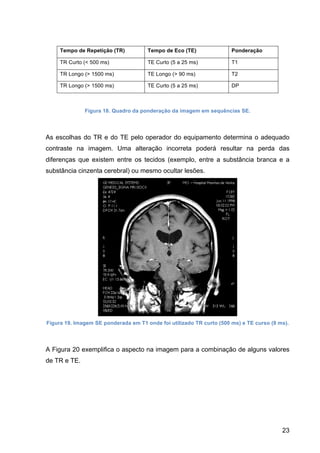

no quadro abaixo da Figura 18.

23

Tempo de Repetição (TR) Tempo de Eco (TE) Ponderação

TR Curto (< 500 ms) TE Curto (5 a 25 ms) T1

TR Longo (> 1500 ms) TE Longo (> 90 ms) T2

TR Longo (> 1500 ms) TE Curto (5 a 25 ms) DP

Figura 18. Quadro da ponderação da imagem em sequências SE.

As escolhas do TR e do TE pelo operador do equipamento determina o adequado

contraste na imagem. Uma alteração incorreta poderá resultar na perda das

diferenças que existem entre os tecidos (exemplo, entre a substância branca e a

substância cinzenta cerebral) ou mesmo ocultar lesões.

Figura 19. Imagem SE ponderada em T1 onde foi utilizado TR curto (500 ms) e TE curso (9 ms).

A Figura 20 exemplifica o aspecto na imagem para a combinação de alguns valores

de TR e TE.